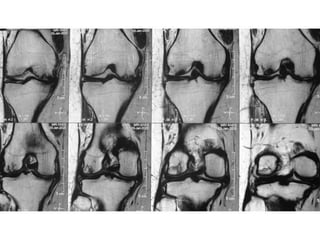

The document presents a detailed case study of a patient with transient osteoporosis of the hip (TOH) and spontaneous osteonecrosis of the knee (SONK) treated at Choithram Hospital & Research Centre in India. Over 20 years, the patient experienced multiple episodes of TOH and SONK with no history of trauma or co-morbidities, resulting in resolutions and recurrences of conditions. The information is intended for orthopedic surgery students and highlights personal experiences and case collections, with a disclaimer regarding content usage and potential controversies.